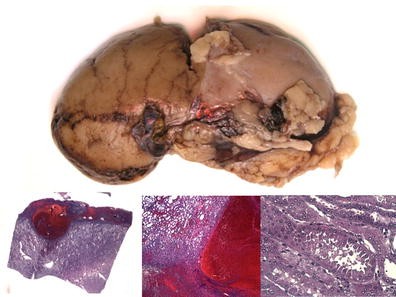

Method: A total of 15 patients with SDHB-mutation were analyzed genomic DNA, clinical data on family history, catecholamine types, tumor metastasis, patient prognosis, and histology of the tumors. Histologic analyses were performed using the new classification named Grading of adrenal pheochromocytoma and paraganglioma (GAPP) classification that was made based on a nationwide Japanese survey. All tumors were scored from 0 to 10 points, and were also graded according to three differentiation types depending on the total score: well (0–2 points), moderate (3–6) and poor (7–10).